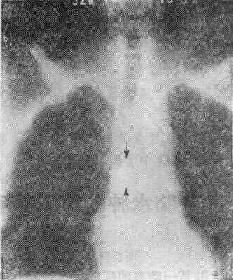

113-3 气道肿瘤(两箭头之间)

(四)占位性病变 ①血肿、脓肿是较常见的原因,如咽后壁脓肿;②肿瘤(图113-37),管腔内或管壁良恶性肿瘤如错构瘤、血管瘤和癌等;③气道附近组织器官的肿瘤,如甲状腺的肿瘤压迫侵犯气道。这类原因引致的气道梗阻,一般是慢性进行性的。然而当气道狭窄的程度超过管径的75%以上,由于附加因素如粘痰等可导致急性气道梗阻,产生严重的呼吸困难,甚至窒息死亡。④异物吸入气官。

(三)X线观察①咽喉部侧位要注意咽喉颈段气管腔道的形态,有无异常的阴影;②胸腔入口区要注意气管形态改变,有无压迫移位及异常软组织影;③气管肿瘤虽然是一种慢性生长的占位性病变,当病变增长占居管腔的75%以上时,由于附加因素如粘痰等可引致急性呼吸道梗阻的症状-阻塞性呼吸困难,如气管错构瘤;④咽部径线和横断面积(CT片)测量,对诊断呼吸睡眠综合征有帮助。